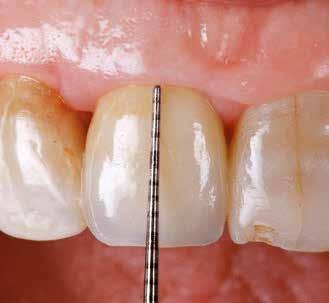

1. ábra: Műtét előtti fogászati panorámafelvétel, amelyen a hiányzó felső állcsont jobb első premolárisát és a szabad véggel rendelkező hidat láthatjuk. — 2. ábra: Az implantátum méreteinek megtervezése CBCT-vel. 3. ábra: Bukkális lágyrészdefektus. — 4. ábra: A biológiai szélesség értékelése a vertikális lágyszövetvastagság alapján. 5. ábra: Palatinális „tekercslebeny” – Palatal roll flap. — 6. ábra: Bredent medical copaSKY 4x10 implantátumbeültetés. 7. ábra: Szubkresztális implantátumbeültetés a várható biológiai szélességnek megfelelően.

8. ábra: Egyéni ínyformázó titánbázison, tulipán alakú emergenciaprofillal. — 9. a. ábra: A sebzárás okkluzális nézete.

bukkális nézete.